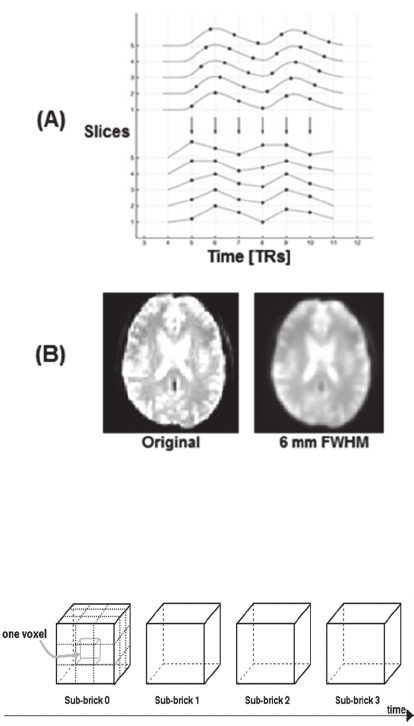

1490580 different voxels. We demonstrate the

structure of the collected data in Figure 3.

Figure 3: 4-Dimensional structure of AFNI format BRIK

(Cox, 1996) file including 3-dimensional dataset over time

sequence.